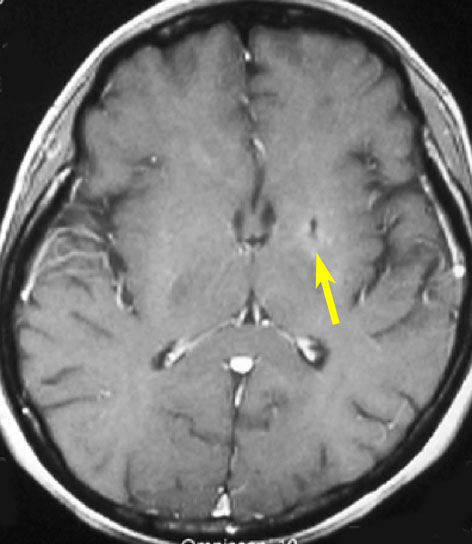

皮膚病変で診断されていた患者さんの同時多発性脳病変

60代女性で,皮膚結節がB cell lymphoma (neoplastic angioendotheliosis)がありました。1年後に急性の認知機能障害と歩行障害がありMRIで発見されたものです。SPECT, PET検査では多発性虚血性病変です。生検手術でIVLの診断が得られました。

左は発症時,右はCHOP化学療法1コース後のT2強調画像です。化学療法で寛解しました。